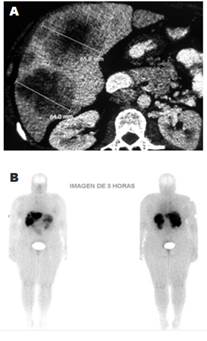

Las pruebas de imagen no invasivas fueron realizadas en todos los casos como primer estudio para localizar el tumor. En orden de frecuencia se realizaron tomografía (n = 16; 84,2 %), resonancia magnética nuclear (RMN) (n = 12; 63,1 %), gammagrafía con análogos de somatostatina (n = 5; 26; 3 %) y, PET 18FDG (n = 1; 5,2 %) (Tabla 2).

En relación con los métodos no invasivos, la tomografía computarizada y la RMN fueron positivas en 56 y 83 % de los casos, respectivamente. Se muestra en la Figura 1 las imágenes de localización de un paciente con insulinoma maligno. La gammagrafía fue positiva en el 60 % de los estudiados, pero solo fue usada en cinco casos del total y ya tenían localizado el tumor con otra imagen adicional. En relación con los métodos del diagnóstico invasivo, tanto la ecografía endoscópica como la prueba de estímulo intraarterial con calcio fueron positivas en el 50 % de los casos, mientras que la ecografía intraoperatoria lo fue en el 100 %. Se muestra en la Figura 2 el cateterismo selectivo de arterias pancreáticas con estímulo de calcio realizado en un insulinoma.